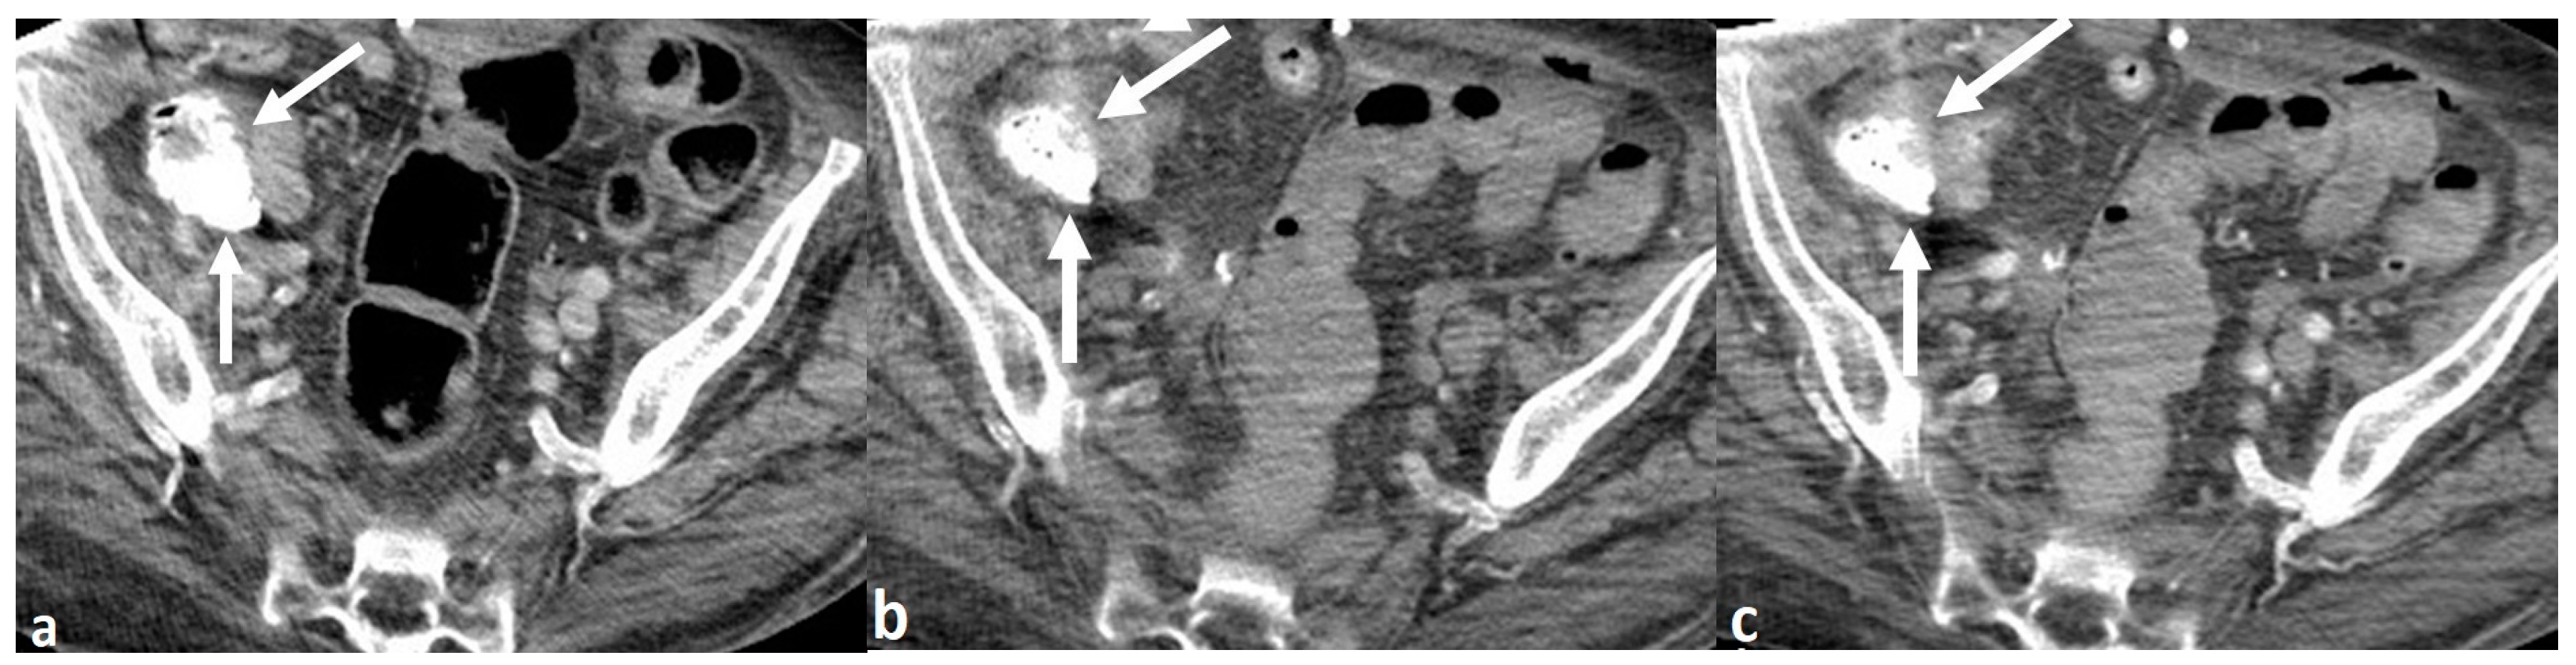

A 72-year-old woman with multiple medical conditions, including end-stage renal disease on hemodialysis, presented to the Emergency Department with rectal bleeding. The patient was found to be hyperkalemic on admission (potassium of 5.7). The patient underwent single-phase portal venous phase CT of the abdomen and pelvis, performed with intravenous contrast and without positive oral contrast. The scan showed hyperattenuating contents in the cecum, which was interpreted by the attending radiologist to be contrast extravasation from an active gastrointestinal (GI) bleed (Figure 1A). There were no other acute or otherwise substantial findings on the scan, including no bowel wall thickening or mass. Based on this interpretation, a multi-phase CT angiogram of the abdomen and pelvis was performed the following day, in which similar intraluminal high density, measuring 1085 Hounsfield Units(HU), was seen in the cecum on the non-IV contrast enhanced series of the examination, performed prior to the administration of intravenous contrast, proving that this was not active bleeding (Figure 1B,C). The arterial and venous phase series from the CT angiogram showed no contrast extravasation anywhere in the GI tract to suggest an acute GI bleed. Subsequent discussion with the clinical team caring for the patient revealed that the patient was being treated with SZC for her hyperkalemia, which explained the source of the hyperattenuating material in the bowel.

Figure 1. 72-year-old woman with rectal bleeding. Axial intravenous contrast-enhanced image from single phase CT (a) shows high attenuation in the cecum (arrows), which was interpreted as active bleeding. Non-IV contrast (b) and arterial phase (c) images from CT angiogram performed one day later again shows hyperattenuating contents (arrows), similar in volume and distribution to the previous CT scan and without change between the two series, proving that the high attenuation was ingested material rather than intravenous contrast extravasation.